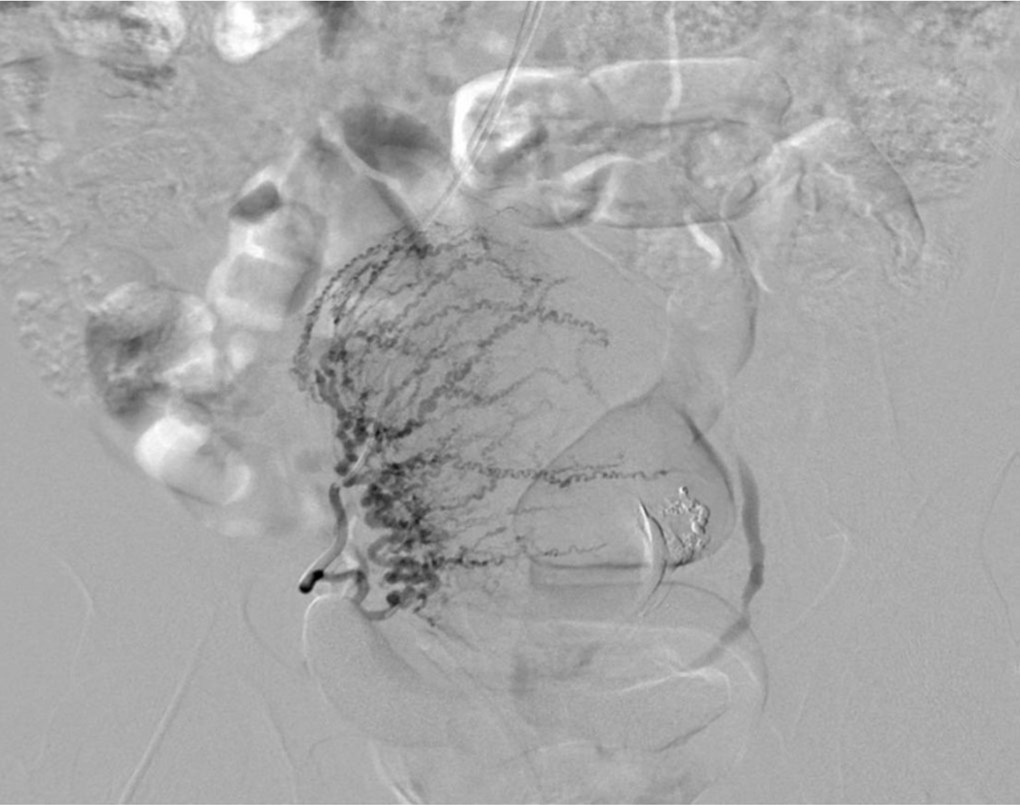

Fig. 4.

A. Left external iliac arteriogram after both uterine artery embolization shows the spring-like appearance of the left round ligament artery (arrow).

B. Selective angiogram of the left round ligament artery shows connection to the distal portion of the left uterine artery(arrow).

이후 신체검진에서 질출혈의 양은 감소하였으나 소량의 질출혈이 지속되었다. RUC catheter로 좌측 외장골동맥을 선택한 후에 시행한 혈관조영술상에서 좌측 자궁원인대동맥(round ligament artery)이 커져 있음을 발견하였다. 좌측 자궁원인대동맥조영술에서 좌측 자궁동맥의 원위부가 조영됨을 확인하였고, gelfoam을 이용하여 좌측 자궁원인대동맥의 색전술을 시행하였다. 이후 신체검진에서 질출혈은 소실되었다.

자궁원인대(round ligament)는 광인대(broad ligament)의 층 사이를 주행하는 띠와 같은 조직으로 그 길이는 10-12cm 정도이며, 자궁의 전방 외측으로 주행한다. 자궁의 전경(anteversion)을 유지시켜주는 것이 그 주된 역할이다. 자궁원인대동맥으로부터 혈류공급을 받게 되며, 이는 서혜인대(inguinal ligament)의 직상방에서 외장골동맥의 분지인 아래배벽동맥(inferior epigastric artery)으로부터 기시한다. 산욕기 출혈의 원인이 되는 가장 주된 혈관은 내장골동맥의 전방분지에서 기시하는 자궁동맥이며, 두 번째로 흔한 원인 혈관은 대동맥의 전외측에서 기시하는 난소동맥이다. 산욕기 출혈에 대한 색전술을 위해 혈관조영술을 시행한 환자의 상당수에서 자궁원인대동맥이 조영되는 것으로 보고되었다(53%, 40/76). 자궁동맥 또는 난소동맥의 색전 후에도 질출혈이 지속되는 경우 자궁원인대동맥이 자궁동맥과 이루는 문합으로 인한 경우가 있으며, 이러한 경우 자궁원인대동맥의 색전이 도움이 될 수 있다. 혈관조영술상 자궁원인대동맥은 아래배벽동맥으로부터 기시하여 자궁 옆으로 상행하는 스프링과 같은 특징적인 모양을 보인다.